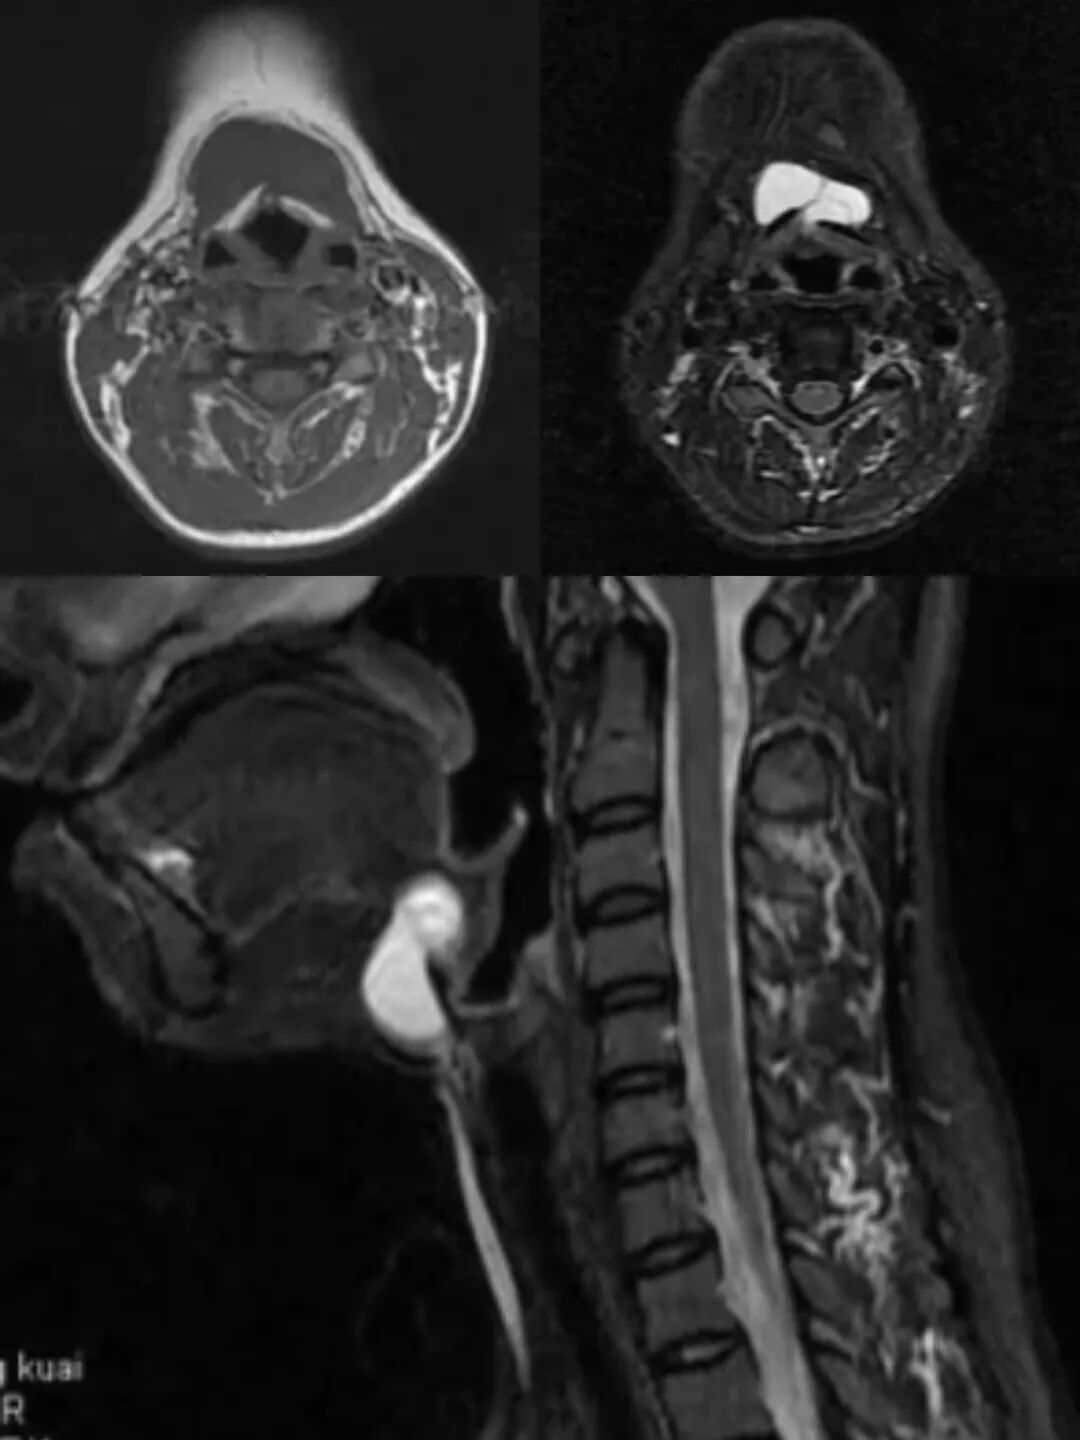

3.MRI检查

◆ T1加权像(T1WI): 囊肿常呈低信号或等信号。

◆ T2加权像(T2WI): 囊肿呈明显高信号,边界清晰。

增强扫描表现与CT增强类似。